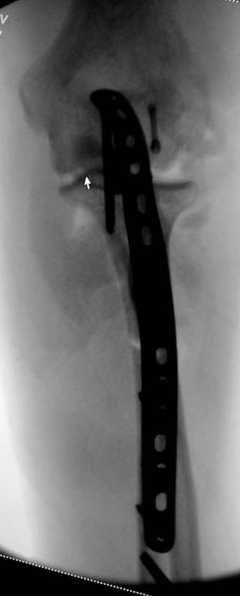

2 вариант

перелом локтевого отростка с переломом головки лучевой кости (использованы 2 мм шурупы)